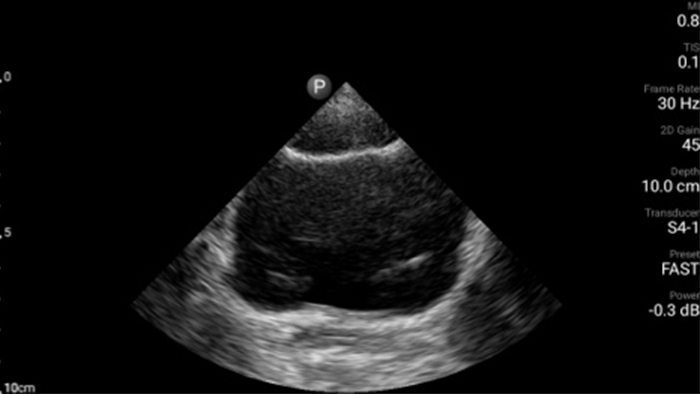

Actúe más rápido para proteger el corazón de sus pacientes

Cuando los segundos cuentan, el ultrasonido portátil puede marcar la diferencia. Lumify puede proporcionar las imágenes de alta definición que requiere cuando y donde las necesite.

Oportunidad de revertir potencialmente la miocardiopatía

Introducción a la ecocardiografía transtorácica